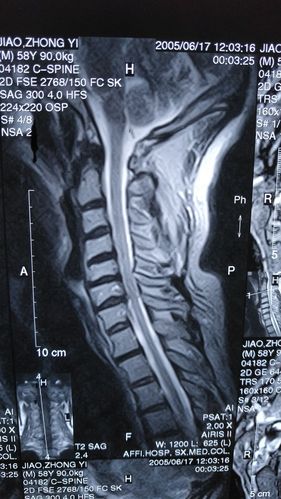

正常颈椎核磁图片解读

正常颈椎核磁图片解读,颈椎病mri图片讲解

颈椎病核磁共振,有没有医生帮忙看看严重吗,应该怎么治疗

2005年所拍颈椎核磁共振照片.

颈椎间盘突出征核磁共振矢状位(mri)

颈3-4节段颈椎病,颈椎管狭窄症,内镜下微创神经减压.

颈椎病核磁报告,请内行给通俗的解读一下.